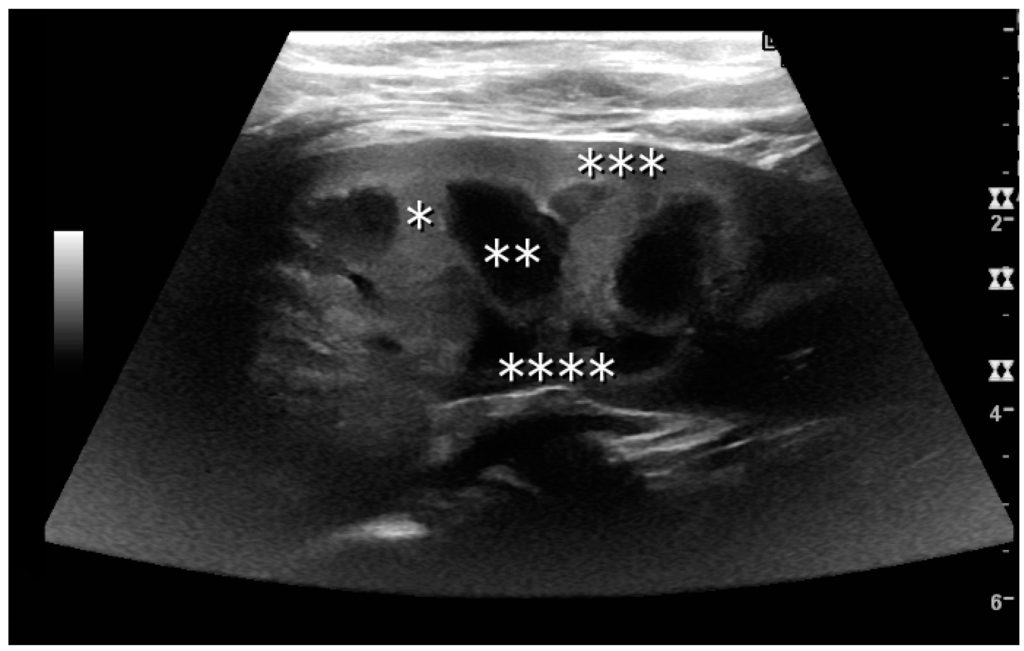

The kidney is divided into parenchyma and renal sinus. The renal sinus is hyperechoic and is composed of calyces, the renal pelvis, fat and the major intrarenal vessels. In the normal kidney, the urinary collecting system in the renal sinus is not visible, but it creates a heteroechoic appearance with the interposed fat and vessels. The parenchyma is more hypoechoic and homogenous and is divided into the outermost cortex and the innermost and slightly less echogenic medullary pyramids [3]. Between the pyramids are the cortical infoldings, called columns of Bertin (Figure 1). In the pediatric patient, it is easier to differentiate the hypoechoic medullar pyramids from the more echogenic peripheral zone of the cortex in the parenchyma rim, as well as the columns of Bertin (Figure 2) [2,4].

Figure 2. Normal pediatric kidney. * Column of Bertin; ** pyramid; *** cortex; **** sinus.